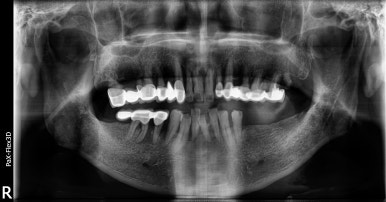

임플란트 픽스처 식립 후

2023-02-27

2023년 2월에 임플란트 1차 수술(인공치근을 식립하는 수술)을 완료했고,

3개월 후인 2023년 5월에 픽스처와 잇몸뼈가 잘 유착되었는지 수치를 통해 확인했습니다.

다행히 일정 수준 이상의 수치가 나와서 뼈와 잘 유착되었다고 평가해 다음 단계인 보철물 수복까지 진행하게 되었는데요.